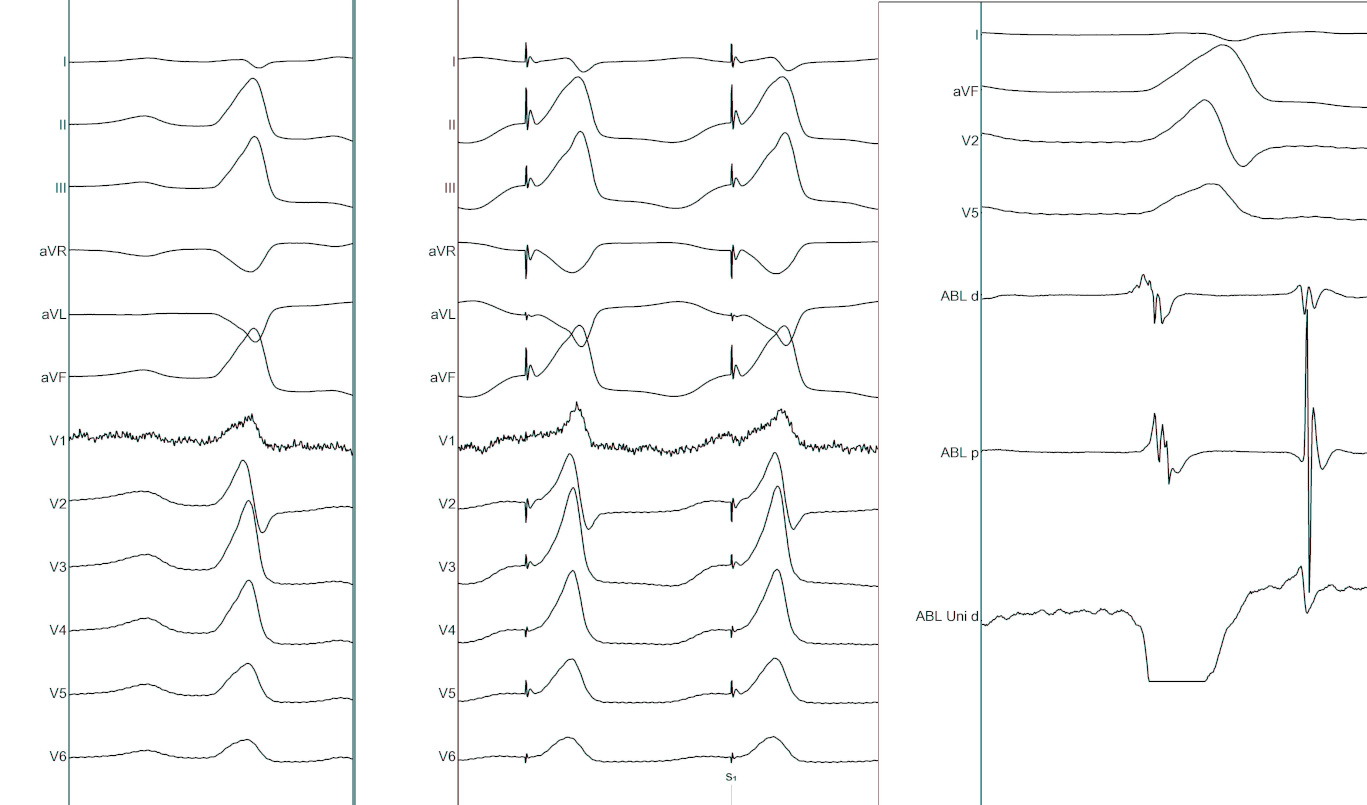

Distinct EGM when mapping above the valve

• Muscle sleeve with fibrous / fatty tissue acting as substrate

• Typically seen above the aortic valve and pulmonary valve

• Late in sinus rhythm and early before PVC

Komandoor S. Srivathsan et al. Mechanisms and Utility of Discrete Great Arterial Potentials in the Ablation of Outflow Tract Ventricular Arrhythmias. Circulation: Arrhythmia and Electrophysiology. 2008;1:30–38

Unipolar EGM

• Concordant with bipolar for RVOT without prior ablation

• May not concur in setting of prior ablation

• May not be useful while mapping above the valve

fig2_new.jpg